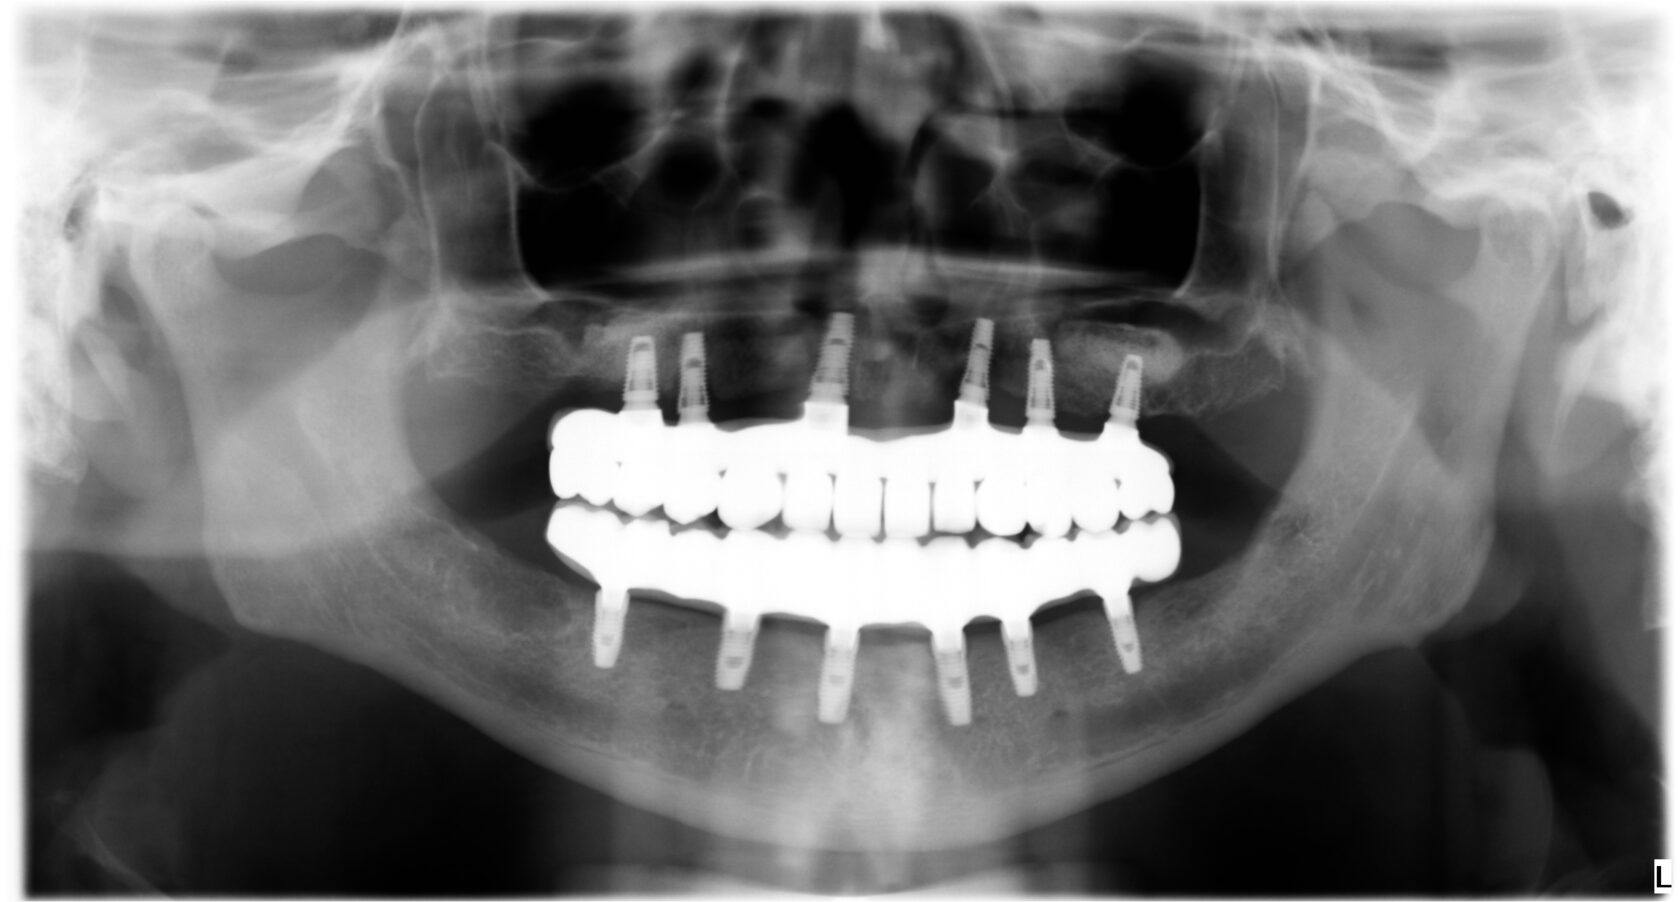

All-on-6

В данном подходе используются шесть имплантатов для закрепления протеза. Это увеличивает стабильность и прочность конструкции, что особенно важно для пациентов с большим жевательным нагрузками или теми, кто предпочитает более жесткий протез.